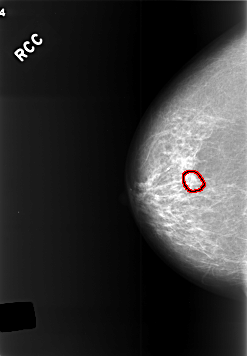

C_0412_1.RIGHT_CC

FILE: C_0412_1.RIGHT_CC.OVERLAY

TOTAL_ABNORMALITIES 1

ABNORMALITY 1

LESION_TYPE CALCIFICATION TYPE PLEOMORPHIC DISTRIBUTION CLUSTERED

ASSESSMENT 3

SUBTLETY 3

PATHOLOGY BENIGN

TOTAL_OUTLINES 1

BOUNDARY